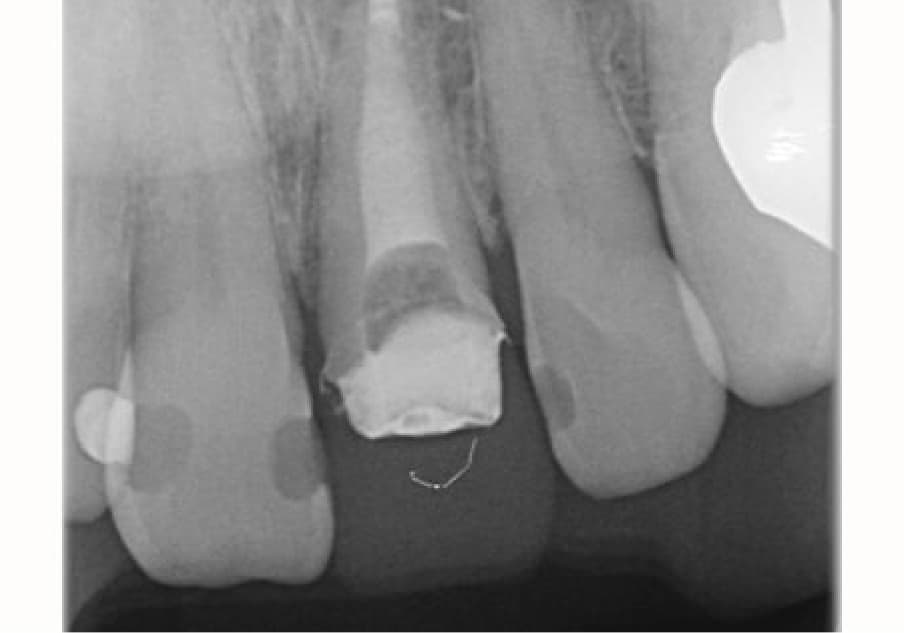

前歯の歯茎が腫れてきた

再根管治療の症例について

20年ほど前に転倒して歯冠破折、歯科を受診し抜髄、補綴処置を受けた。1ヶ月位前に腫脹を確認して歯科を受診、当院へ紹介されました。

| 主訴 | 前歯の歯茎が腫れている | 診断 | 慢性化膿性根尖性歯周炎 |

| 治療時年齢 | 57歳 | 性別 | 男性 |

| 治療期間/回数 | 1ヶ月ほど | 費用 | 22万円(税込み) ※紹介のため、補綴は行っておりません |

| 治療時の注意点 | 再根管治療となるので、必然的に初回の根管治療より、成功率が下がりやすい傾向があります。 ※自由診療の範囲となります。 |